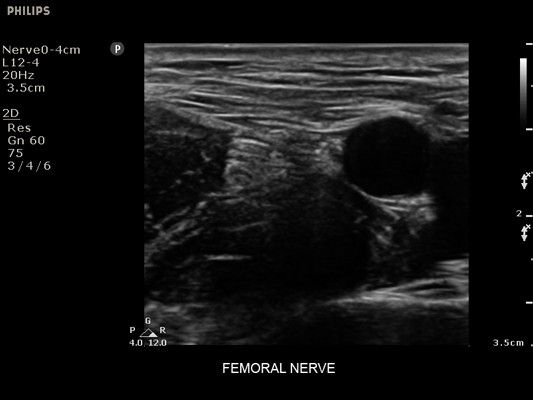

• Диагностика нервов

• Улучшение визуализации иглы для линейных датчиков - Да

• Линейный УЗИ датчик Philips L12-4